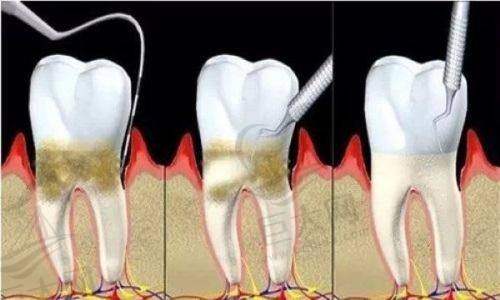

与宣城其他口腔医院相比,宣城大医口腔有着自己独特的优势。和宣城宛陵口腔相比,虽然宛陵口腔在种植牙和牙齿矫正方面也有出色表现,且有特别多真人种植矫正病例,价格保持中等价位,但宣城大医口腔的数字化优势更为明显。其数字化种植牙和数字化牙齿矫正技术在精细度和成效上可能更胜一筹。和宣城为民口腔相比,为民口腔医生队伍有一定实力,在种植和美学矫正方面也不错,且是连锁牙科机构,但宣城大医口腔作为二级专科口腔医院,在专精性和规范性上可能更具保护。和宣城市口腔医院相比,市口腔医院医疗设备齐全,消毒工作到位,擅长隐形正畸、金属正畸和牙齿种植手术,但宣城大医口腔的数字化特色项目是其独特的竞争力。和宣城维佳康口腔相比,维佳康口腔在根管治疗、牙周疾病治疗等方面有一定优势,而宣城大医口腔的特色项目则更侧重于数字化的种植牙和牙齿矫正。